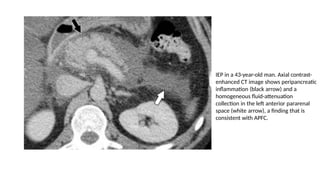

IEP in a 43-year-old man. Axial contrast-

enhanced CT image shows peripancreatic

inflammation (black arrow) and a

homogeneous fluid-attenuation

collection in the left anterior pararenal

space (white arrow), a finding that is

consistent with APFC.